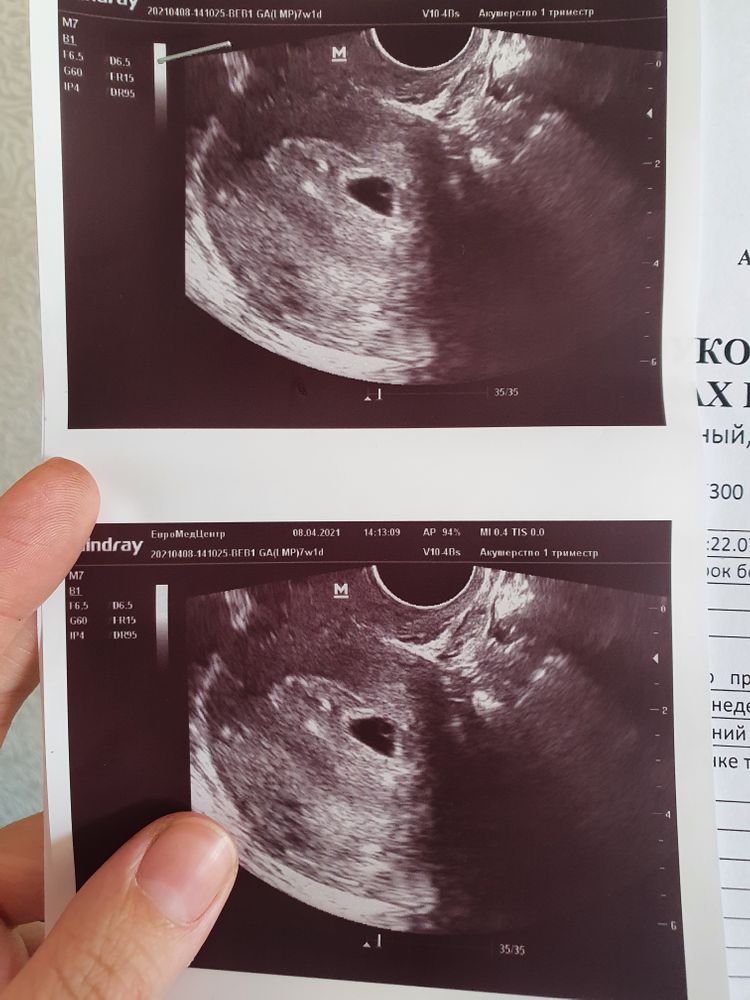

7 недель ❤

Сходила на первую встречу с малышом😇 узнать как он там, где закрепился, как развивается.

Срок ещё совсем маленький, поставили 4 недели эмбриональных) но сказали уже через 2 недельки идти вставать на учёт. И начнутся снова эти анализы, баночки, сдача крови и прочее 😅